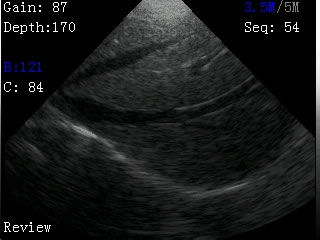

我司最新推出的V2型腕式B超,主机重量仅140克,看成目前全世界最轻的B超。

V2型腕式扇扫B超由主机、探头、外置电池、手握式键盘组成,重量只有140g(不含探头和电池)堪称全世界最轻的B超。

-扫描方式:机械扇扫

-探头频率:3.5MHz/5MHz双频率可变频探头

-扫描深度:≥180mm,70、110、130、150、192mm五档可调